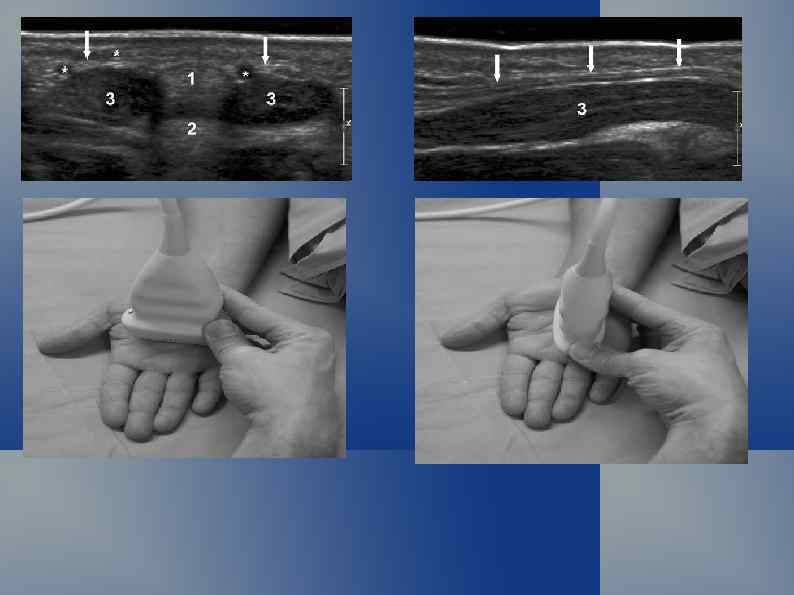

Синдром карпального канала

Нормальная ультрасонографическая картина Срединный нерв в норме и при синдроме карпального канала.